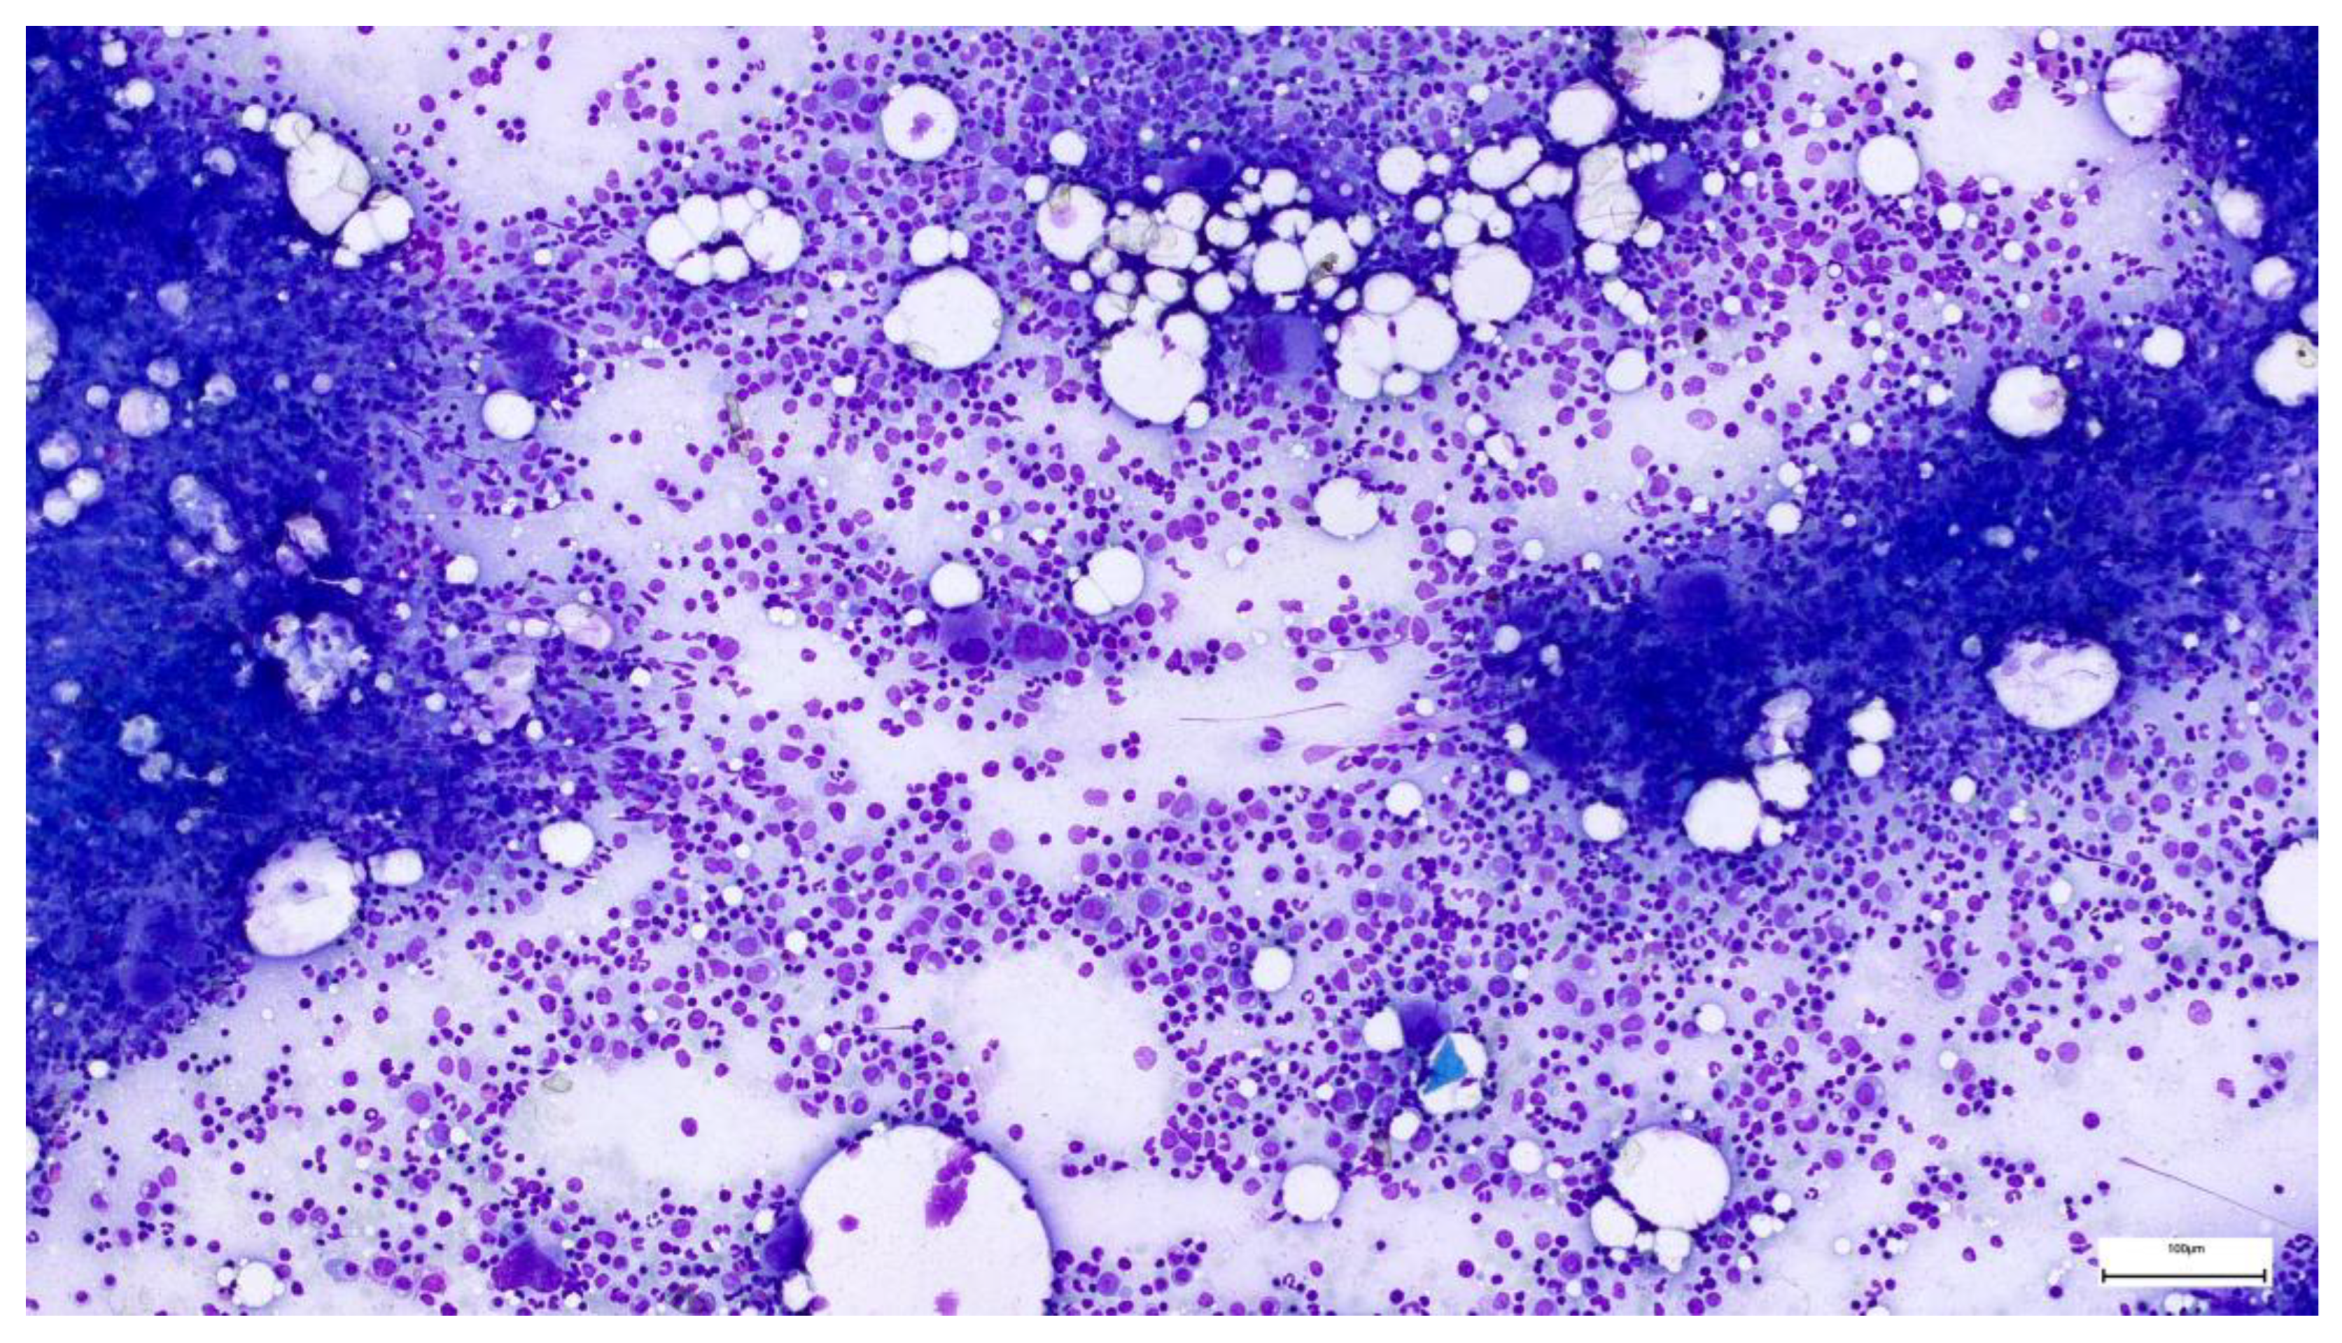

2.3. Hematological Evaluation and Investigation